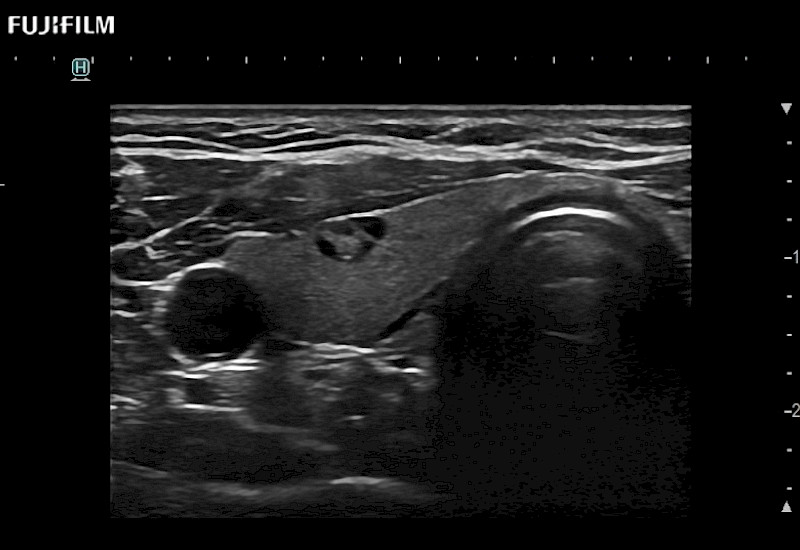

Extraordinary high-resolution digital imaging

- Exceptional near and far-field resolution

- Instant feedback on tumor margin delineation

- Valuable information to guide tumor resections

- Exceptional near and far-field resolution

- Instant feedback on tumor margin delineation

- Exceptional near and far-field resolution

- Instant feedback on tumor margin delineation